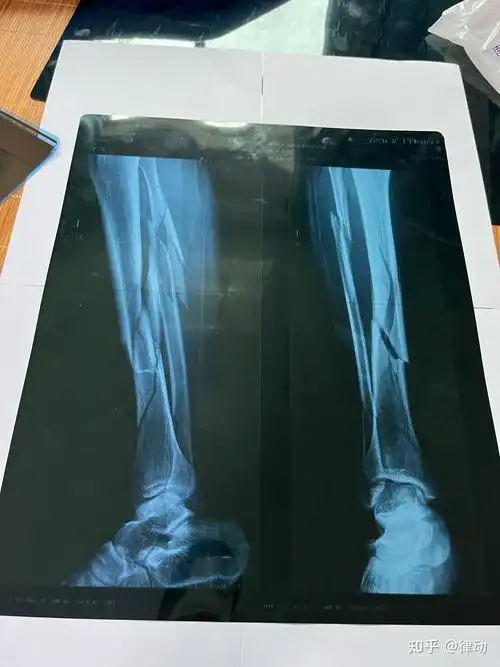

左小腿胫腓骨粉碎性骨折整个历程记录 - 知乎